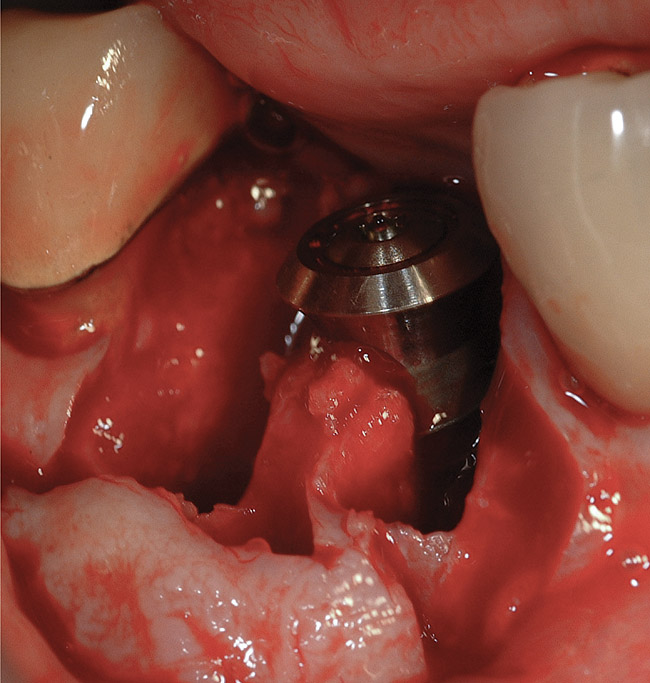

Implant placement at the time of mandibular molar extraction should never be attempted if there is any doubt about the ability to place an ideal dimension implant in the appropriate restorative position and attain primary stability. In such a situation it is better to first perform regenerative therapy at the time of tooth removal and place the implant in a subsequent surgical session (Figure 2 through Figure 4).

All mandibular multi-rooted teeth are hemisected (or trisected in the rare cases of three-rooted mandibular molars) prior to removal. In such cases, a piezosurgical approach is utilized, in conjunction with specifically designed periotomes, to effect atraumatic tooth extraction. If such therapy is performed appropriately, the net result is an extraction socket whose alveolar morphology has been no further compromised through the act of tooth removal. In situations where high-speed rotary instrumentation must be used to help retrieve fractured root portions, the site is deemed no longer amenable to immediate implant placement due to the excessive trauma having been placed on the alveolar bone in the area. Regenerative therapy is performed employing appropriate graft materials and covering membranes, and the implant is placed in a second surgical visit. Such instances are rare.

Following tooth extraction, the defect is thoroughly debrided, and the extent and morphology of alveolar bone destruction are assessed. The presence or absence of periapical and/or periodontal inflammatory lesions prior to defect debridement plays no role in the determination of whether or not to immediately insert an implant. Rather, it is the morphology and quantity of residual alveolar bone in the extraction socket area that determines whether or not an implant will be placed at the time of tooth extraction.

Although ideal implant positioning may be attained in the vast majority of situations at the time of extraction of a mandibular molar, it is imperative that the surgical site is assessed after tooth removal and defect debridement is accomplished.